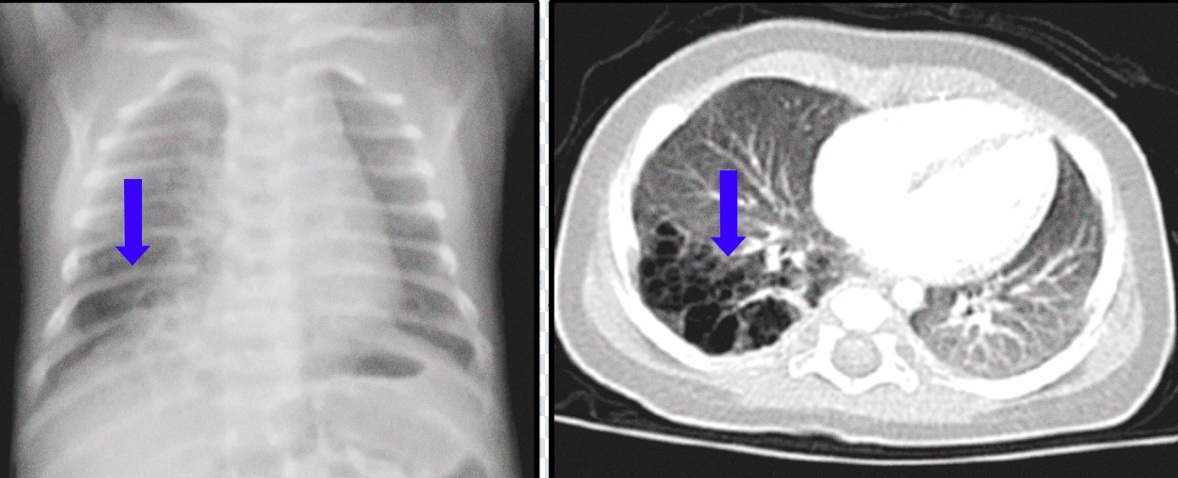

Mal formação adenoide cística (MAC) ou malformação pulmonar congênita da via aérea (CPAM)

Corresponde até 70%da malformações

Benigna

Formação de cistos pulmonares que contém muco, cels epiteliais, tecido glandular.

Mais comuns nos lobos inferiores

Frequentemente em bebês e crianças

Classificação de Stocker

- I: predomínio de cistos grandes

-II: cistos < 1cm

-III: microestruturas que mimetizam bronquíolos terminais e alvéolos

DX é feito pela us prénatal

Tratamento é cirúrgico com resseccao do lobo (lobectomia) comprometido (prinicpal indicacao em sintomatico)